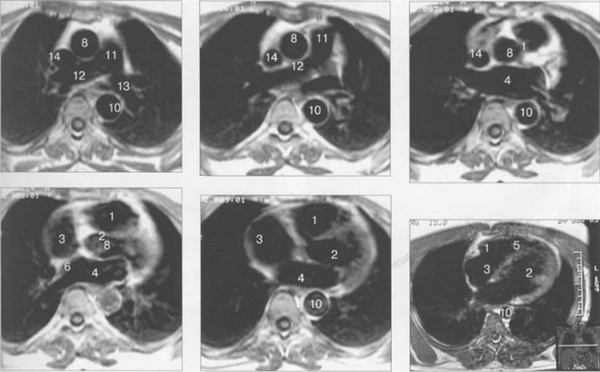

МРТ АНАТОМИЯ СЕРДЦА

МРТ позволяет получать изображения сердца в поперечной (аксиальной), фронтальной (корональной) и сагиттальной плоскостях (ортогональные сечения). Поскольку анатомические оси сердца и магистральных сосудов (за исключением аорты в нисходящем отделе и полых вен) не совпадают со стандартными ортогональными плоскостями исследования, общепринятыми при исследованиях других органов и систем организма, для МРТ-исследования сердечно-сосудистой системы разработаны дополнительные наклонные срезы (двухкамерное сечение, четырехкамерное сечение, сечение по короткой оси левого желудочка).

Рис. 9.47. МРТ сердца. Аксиальная плоскость.

Здесь и на рис. 9.48—9.52:

I — правый желудочек, 2 — левый желудочек, 3 — правое предсердие, 4 — левое предсердие, 5 — межжелудочковая перегородка, 6 — межпредсердная перегородка, 7 — задняя стенка левого желудочка, 8 — восходящая часть аорты, 9 — дуга аорты, 10 — нисходящая часть аорты, 11 — легочный ствол, 12 — правая легочная артерия. 13 — левая легочная артерия, 14 — верхняя полая вена, 15 — нижняя полая вена, 16 — трахея.

Рис. 9.48. MPT сердца. Сагиттальная плоскость.

Рис. 9.49. МРТ сердца. Двухкамерные сечения.

Рис. 9.50. МРТ сердца. Фронтальные сечения.

Рис. 9.51. МРТ сердца. Сечения по короткой оси левого желудочка.

Рис. 9.52. МРТ сердца. Четырехкамерные сечения.

На рис. 9.47—9.52 представлены Т1-ВИ наиболее часто используемых МР-сечений сердца.